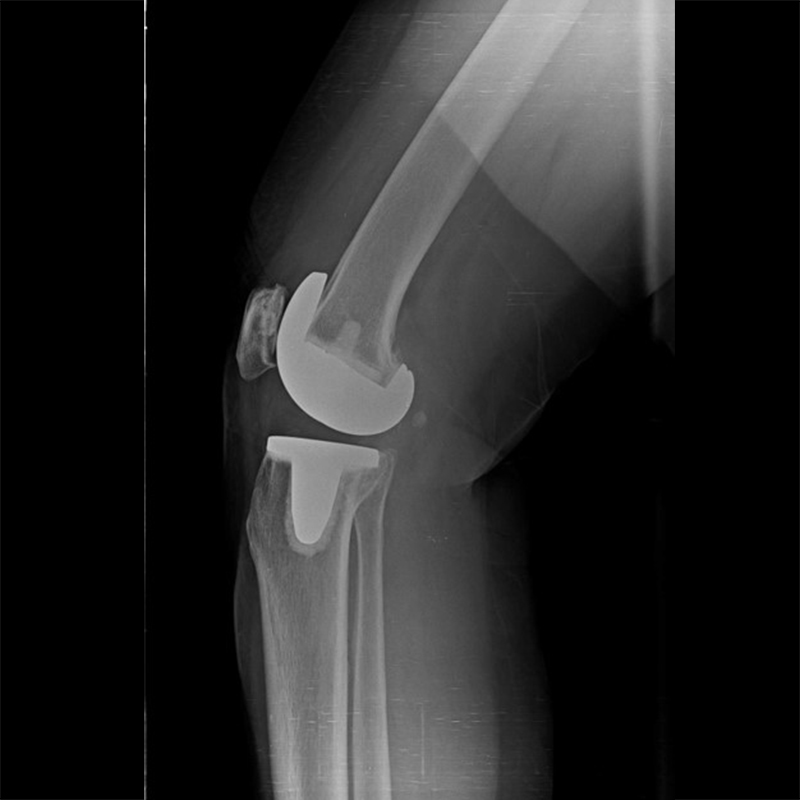

外院失敗本院再置換 首頁 案例分享 膝關節手術 外院失敗本院再置換 蕭女士 69歲 術前 術後 81歲 林女士 術前 術後 蕭女士 69歲 術前 術後 鄒女士 69歲 術前 術後 李女士 74歲 術前 術後 吳女士 71歲 術前 術後 謝女士 65歲 術前 術後